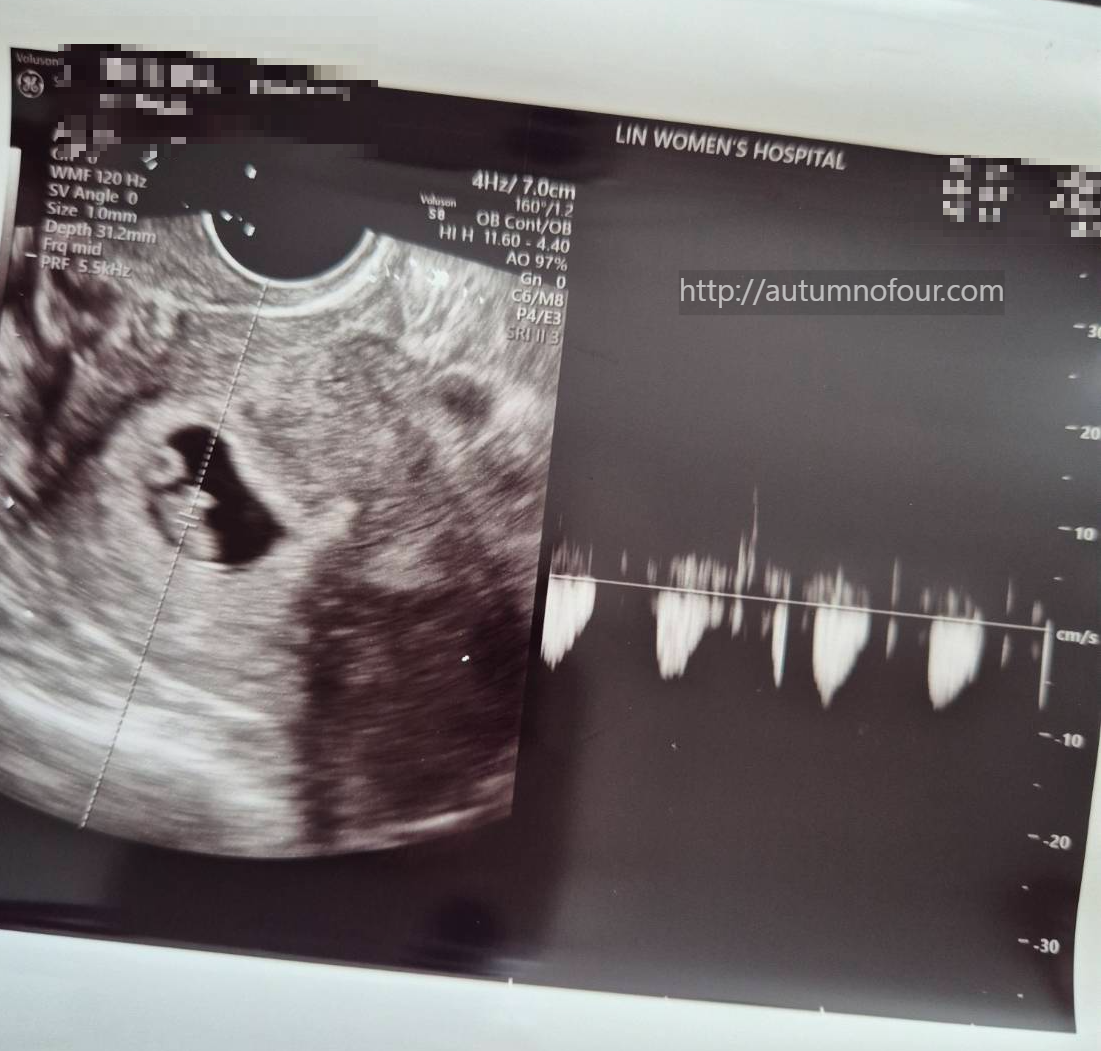

- 심장소리 확인 (초음파), 약처방, 산모검사

그리고 오늘은 특별히 실시간으로 초음파 화면을 보여주셨다.

그리고 쿵쾅쿵쾅 심장소리까지... !

심장소리도 좋고 아주 잘 크고 있다는 이야기를 들었다.

이제부터 진료보면서 찍은 초음파 영상과 심장 소리까지 어플로 언제든지 들을 수 있게 되었다.